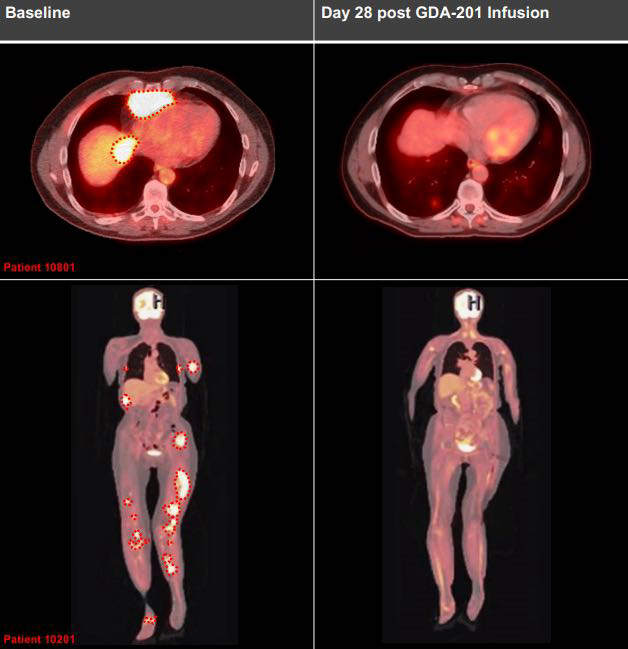

- 淋巴瘤治疗

:在GDA-201(一种NK细胞疗法候选药物)的临床试验中,7例B细胞淋巴瘤患者的肿瘤负担明显减轻,其中3例实现了完全缓解,即体内已检测不到肿瘤病灶。